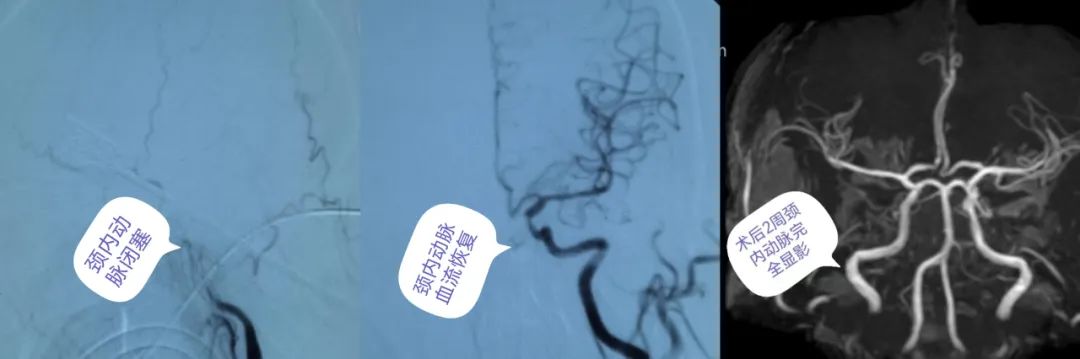

医生当机立断,“必须立刻准备取栓!”与胡大爷的家属充分沟通后,家属同意手术治疗,随后迅速将患者送入导管室。术中脑血管造影显示,左侧颈内动脉闭塞,卒中中心介入团队利用抽吸导管,成功取出暗红色的血栓,颈内动脉眼段重度狭窄,用球囊予以扩张成形,使患者闭塞的血管得到及时的再通,血流恢复正常。目前胡大爷语言、右侧肢体肌力恢复正常,已经行走着出院。